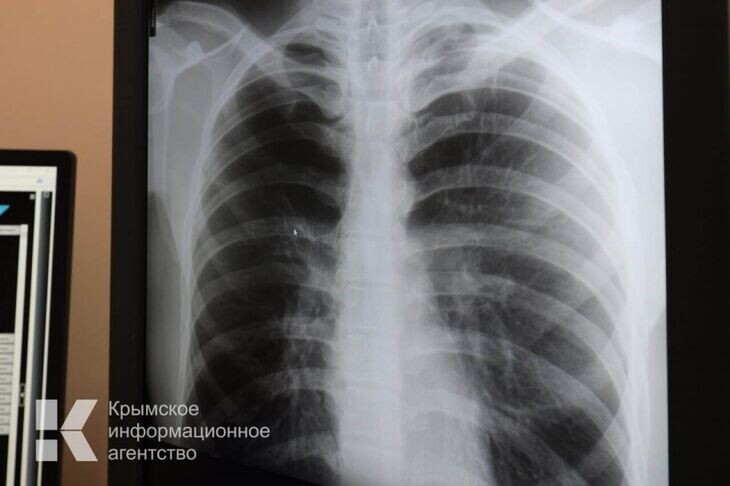

На диспансерном учёте с хронической болезнью лёгких состоят 17 тысяч крымчан

Одним из самых распространённых заболеваний в мире является хроническая обструктивная болезнь лёгких, сокращённо – ХОБЛ.

К симптомам заболевания относятся кашель, иногда с мокротой, затруднённое, свистящее дыхание и повышенная утомляемость.

Как сообщил корреспонденту «Крымской газеты» заместитель министра здравоохранения РК Антон Лясковский, по состоянию на 31 декабря 2024 года на диспансерном учете в медицинских организациях, подведомственных министерству, состояло 17 307 пациентов с ХОБЛ.

«Пациентам с факторами риска развития ХОБЛ, прежде всего курильщикам, рекомендуется ежегодно проводить спирометрию. Снижение такого показателя как ОФВ1, проверяемого при данном обследовании, на 60 мл/год свидетельствует о формировании обструкции. Важно спирометрию проводить с бронхорасширяющей пробой», - предупредил Лясковский.